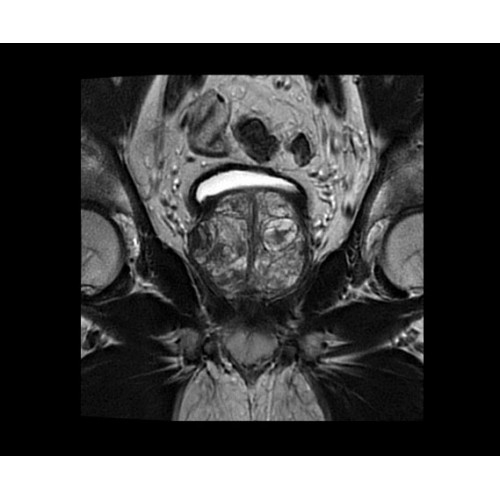

Поле обзора 50x50x50 см и апертура шириной 70 см позволят достоверно визуализировать сложные анатомические области для пациентов с крупным телосложением, например, плечи и бедра. Феноменальная однородность системы SIGNA Architect обеспечивает наиболее широкое поле обзора с улучшенными характеристиками градиентов. Ничто не останется незамеченным.

• OrthoWorks — программное решение для визуализации структур опорно-двигательного аппарата с прекрасным контрастированием тканей.

• BodyWorks — для визуализации абдоминальной и тазовой областей, подстраиваясь под запросы пользователя с учетом любых типов пациентов.